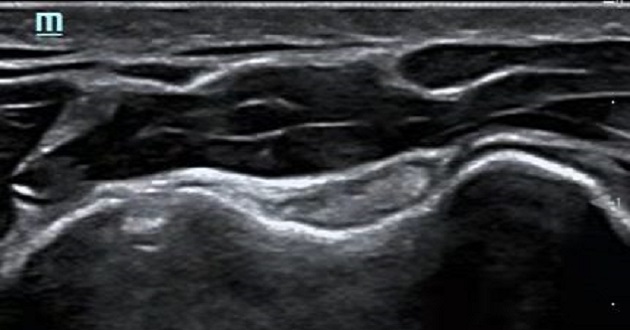

So, how does ultrasound work in treating sports injuries? Due to competitive edges such as security, convenience, minimal invasion, and lack of radiation, ultrasound is widely used to systematically and thoroughly check patients over. It has better resolution than CT and MRI for the fine structures of soft tissues, and can be performed in a short period of time and used for long-term follow-up, contributing to the diagnosis and treatment of sports injuries in athletes and the general public. In the Peking University Third Hospital, a designated hospital for the Winter Olympics, Mindray's high-end portable ultrasound M9 and M7 help doctors diagnose patients after sports traumas.

Mindray's specialized musculoskeletal (MSK) ultrasound solutions provide physicians with a set of cutting-edge, professional, and comprehensive ultrasound innovative support services.?Mindray's proprietary ZST+ Platform known as the zone sonography and 20MHz UHF probe serve as the breakthrough technologies for excellent imaging.?CEUS, shear wave elastography and other comprehensive high-end features can not only meet the current clinical needs, but also be able to scale up for the future needs. Various advanced puncture functions make it possible to achieve one-stop future musculoskeletal diagnosis and treatment solutions.